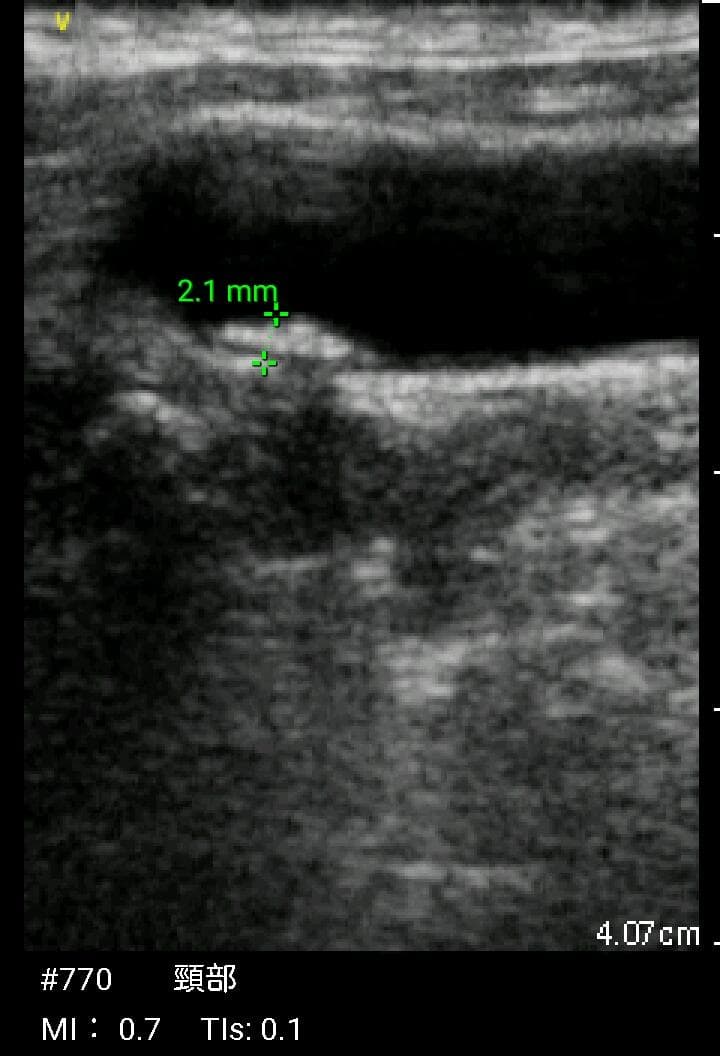

おわかりになる方のみの購入をお願いいたします実際に実施した写真をあげました正常肝臓、胆石症、頸動脈プラーク、同じく頸動脈プラーク、Mrの収縮期、同じくM弁の開放期とA弁の開放期、腹部大動脈瘤、正常の頸動脈、甲状腺右葉の結節、前立腺肥大画像の描出は条件によりますがご検討をお願いいたします経年変化、使用に伴うスレや傷などがあります機能に問題はありませんスキャンは心血管、腹部、体表に対応します外部接続端子のカバーが一部壊れていますが蓋は閉まりますバッテリーはフル充電されますが劣化はあると思います医療用モニタリング機器 Vscan Extend、GE- モデル名: Vscan Extend- ブランド: GE- 色: ホワイト- 機能: 医療用モニタリング機器ご覧いただきありがとうございます。。[新品未使用品]KT TAPE ブラック 25cm プレカット 150枚入